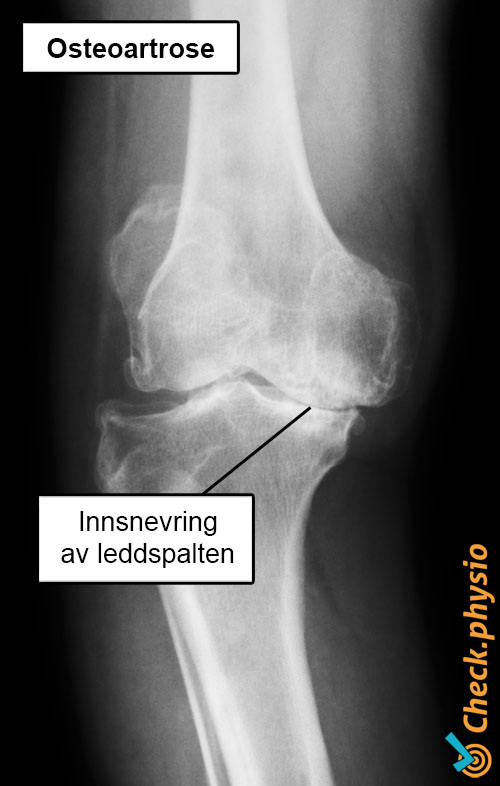

Legen eller fysioterapeuten stiller først en rekke spørsmål for å finne ut hva plagene består av, og hvordan de har oppstått. Deretter følger en fysikalsk undersøkelse. Ved kneslitasje kan røntgenbildet vise at leddspalten har blitt trangere. Eventuell osteofyttdannelse kan også ses. Røntgen tas kun dersom det fortsatt er usikkerhet rundt diagnosen etter fysikalsk undersøkelse, eller hvis funnene på røntgen påvirker behandlingen.